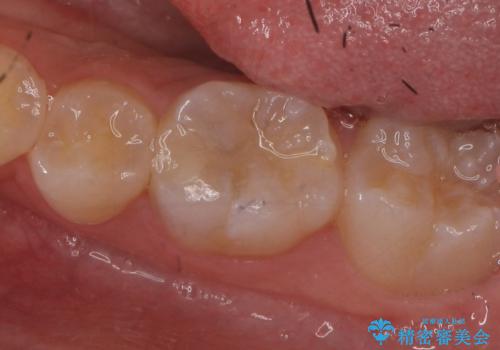

- 左下奥歯がしみるので診て欲しいといらっしゃった方の症例です。

古い樹脂と虫歯を除去後、セラミックインレーによる修復を行いました。